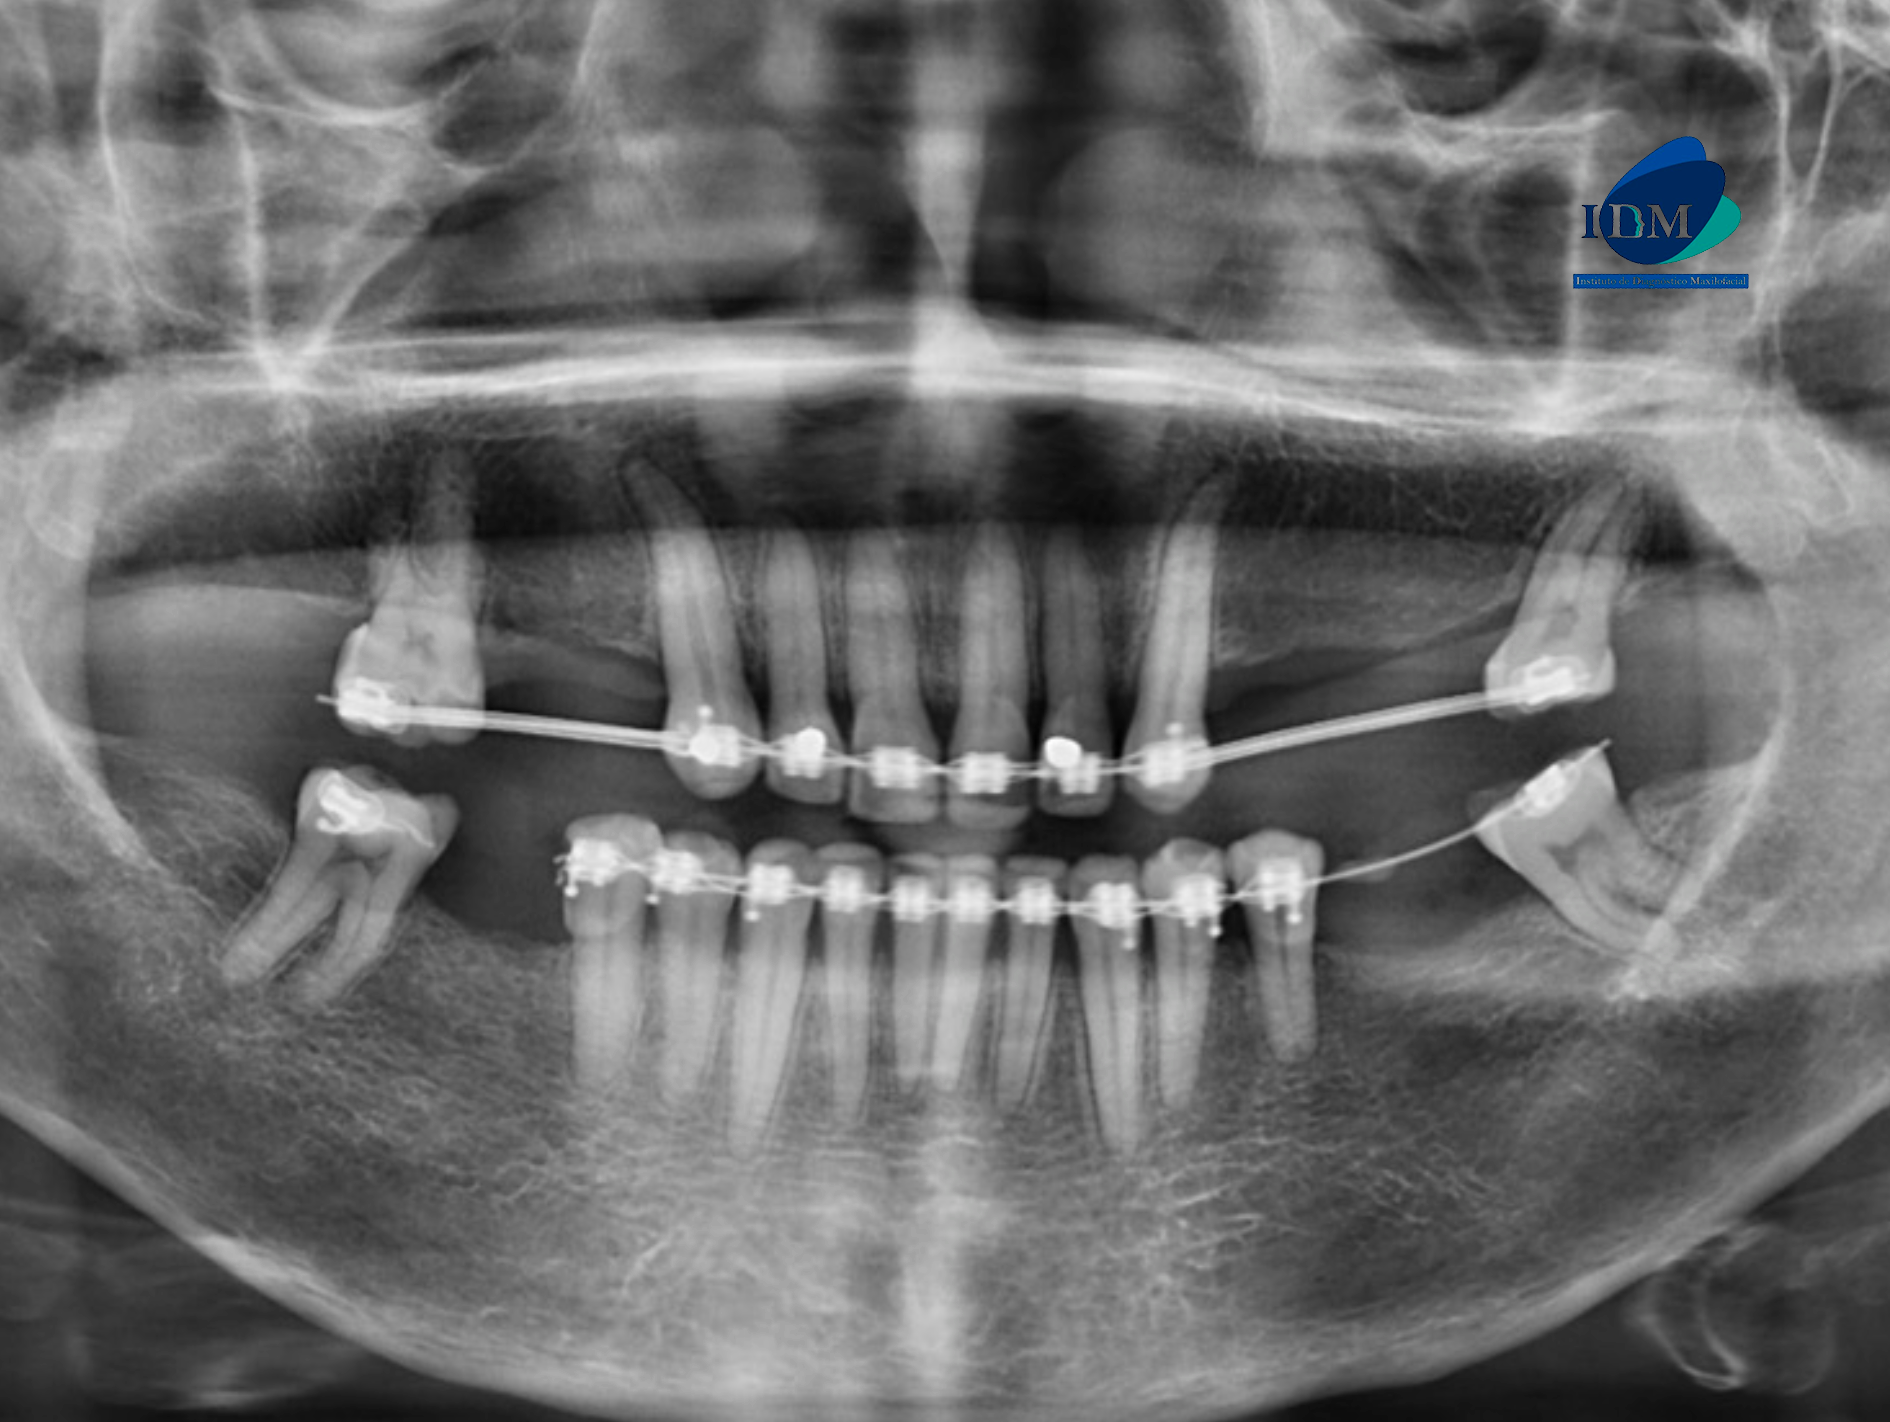

Paciente femenino de 58 años acude al Instituto de Diagnostico Maxilofacial para realizarse una tomografía para la colocación de implante dentales. A la evaluación de la radiografía panorámica se observa paciente edéntulo parcial y dispositivo de ortodoncia fija en piezas del maxilar superior e inferior, asimismo se observa la bifurcación del conducto dentario inferior del lado derecho que se extiende hacia la zona retromolar (variante anatómica)

Radiografia Panorámica